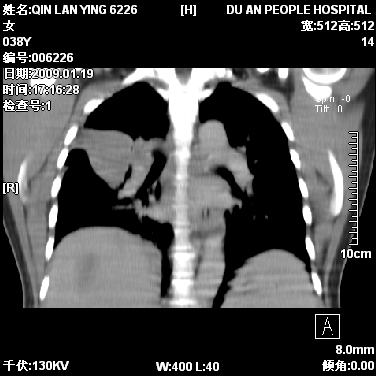

女,38岁,胸疼1个月。wbc:1万4

1)右肺中央型肺癌并右肺上叶阻塞性肺炎、节段性肺不张,纵隔淋巴结转移、右侧胸膜转移、肝脏转移。2)右侧胸腔少量积液。

1、右侧中央型肺癌并阻塞性肺不张,纵隔内、主动脉弓旁、右肺门淋巴结及肝脏转移可能性大,建议纤支镜进一步检查。

2、右侧胸腔积液。

本病例有几个容易诊断的地方:1、右肺上叶前段支气管闭塞,肺不张。2、淋巴结明显肿大。3、肝脏多个类圆形低密度影呈“牛眼征”改变,高度提示转移。

从影像学角度分析      右肺上叶中央型肺癌,并阻塞性不张、肺炎,纵隔淋巴结、膈顶淋巴结转移。

肝内两个大小不等低密度结节,内可见更低密度影,首先考虑肝内转移瘤,但联想到患者wbc1万4,建议楼主还是做个增强比较明确,除外肝脓肿的可能。